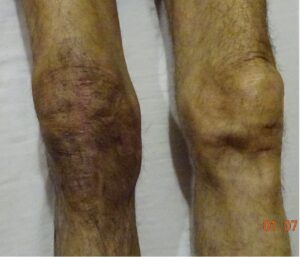

The International Association for the Study of Pain (IASP) has defined CRPS-1 as ‘‘a variety of painful conditions following injury which appears regionally, having a distal predominance of abnormal findings, exceeding in both magnitude and duration the expected clinical course of the inciting event often resulting in significant impairment of motor function and showing variable progression over time”. It has been called CRPS-2 when it occurs when an obvious nerve damage. can be demonstrated. IASP goes on to describe CRPS as a chronic, progressive disease characterized by severe pain, motor impairment, and “inflammation like” changes in the distal extremity. The CRPS limb is very painful, looks angry, red and is swollen as if there is some infection and inflammation (figure 1). Inflammatory mediators are found to be raised in the venous blood draining the CRPS limb. However, there is no infection because all the tests that suggest an infection like a raised white blood cell count, or pus collection are negative.

Figure 1: The typical appearance of CRPS limbs and face with color, temperature and size asymmetry

Figure 1: The left hand is swollen, hot, stiff and painful, the operated right knee looks much darker, warm and extremely stiff and painful, operated right ankle swollen, dark, painful and unable to bear weight . The last image shows a swollen dark and extremely painful face due to CRPS after cancer surgery.